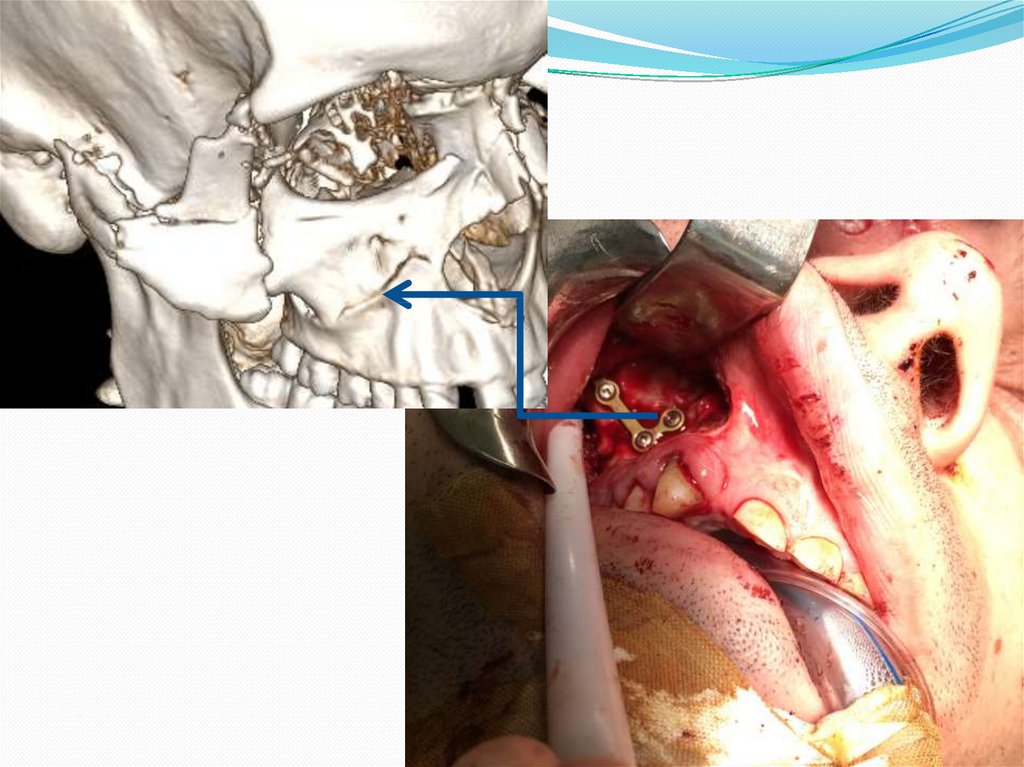

12. Клинический случай № 2! Поскользнулся, упал, потерял сознание, очнулся …

Пациент С. 40 лет.